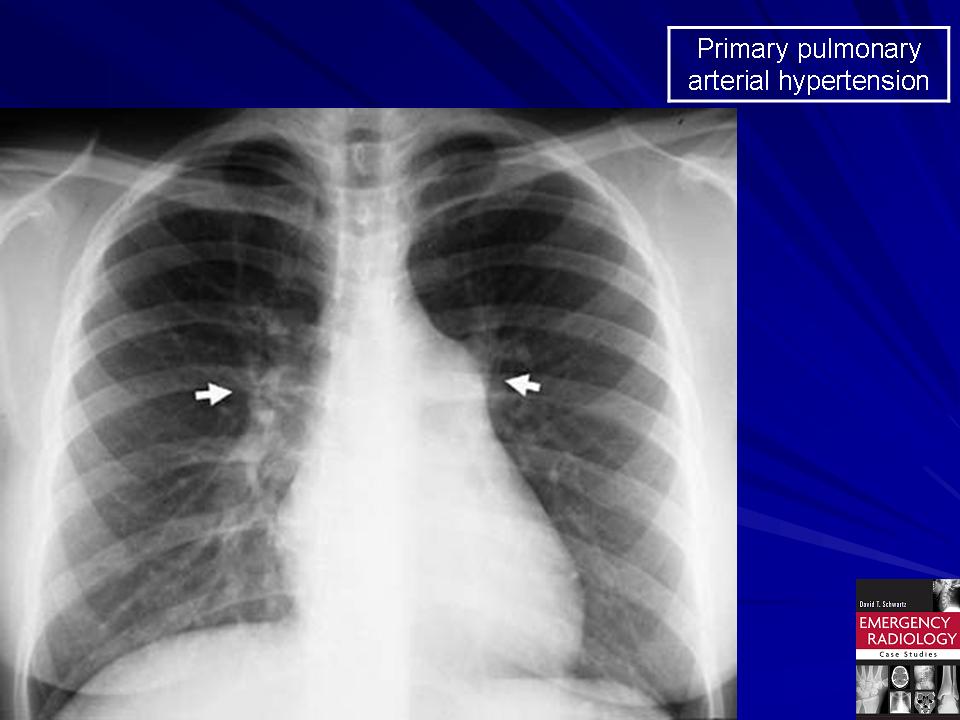

Рентгеновские снимки тератомы средостения: Диагностика и лечение

Раздел: Фотоэссе